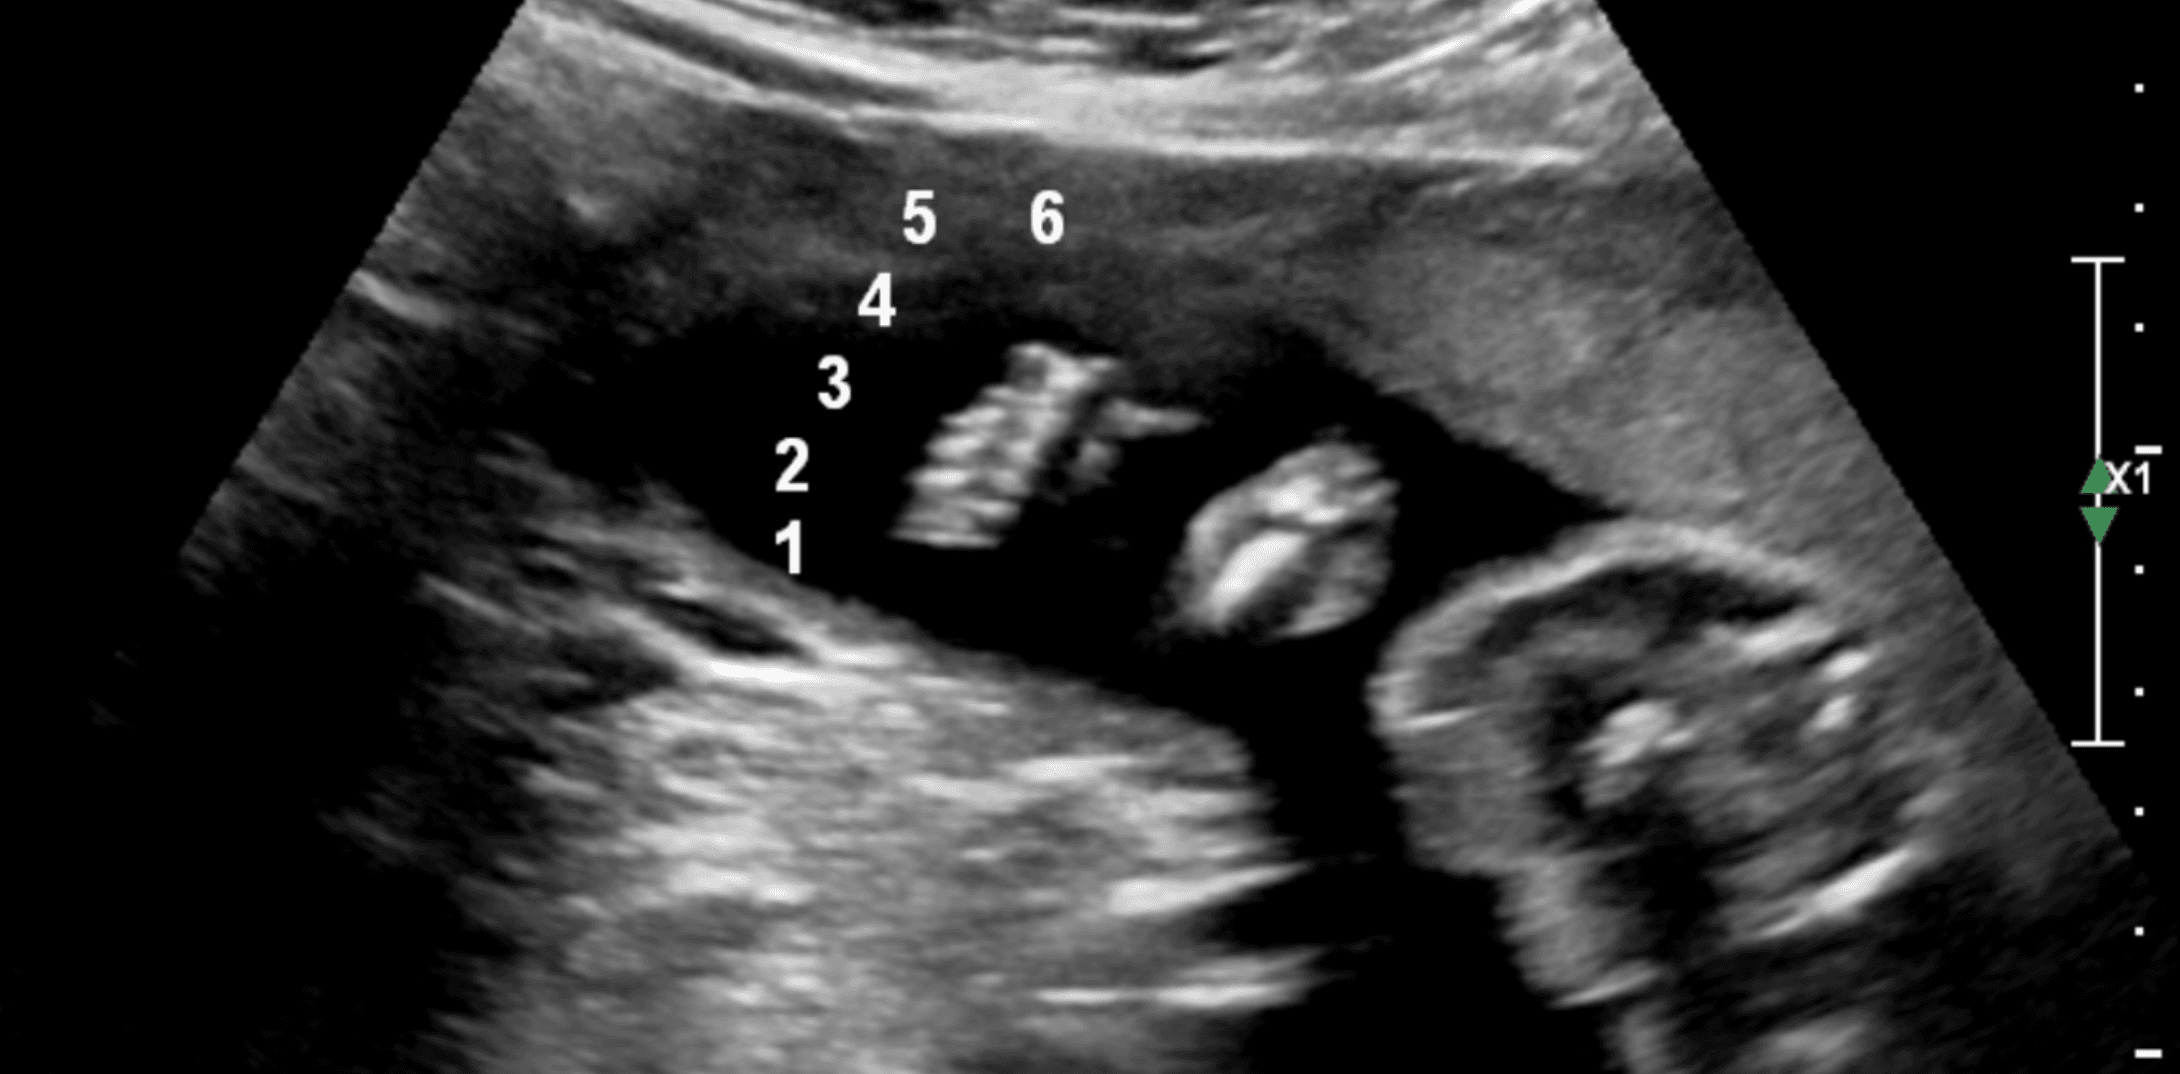

During this detailed anatomy scan performed at 20 weeks of gestation, we identified something special — an extra digit on the foot.

No matter if you have 5 or 6 toes, we love each and every one of them.

- Limbs: arms, legs, hands, and feet — including counting fingers and toes